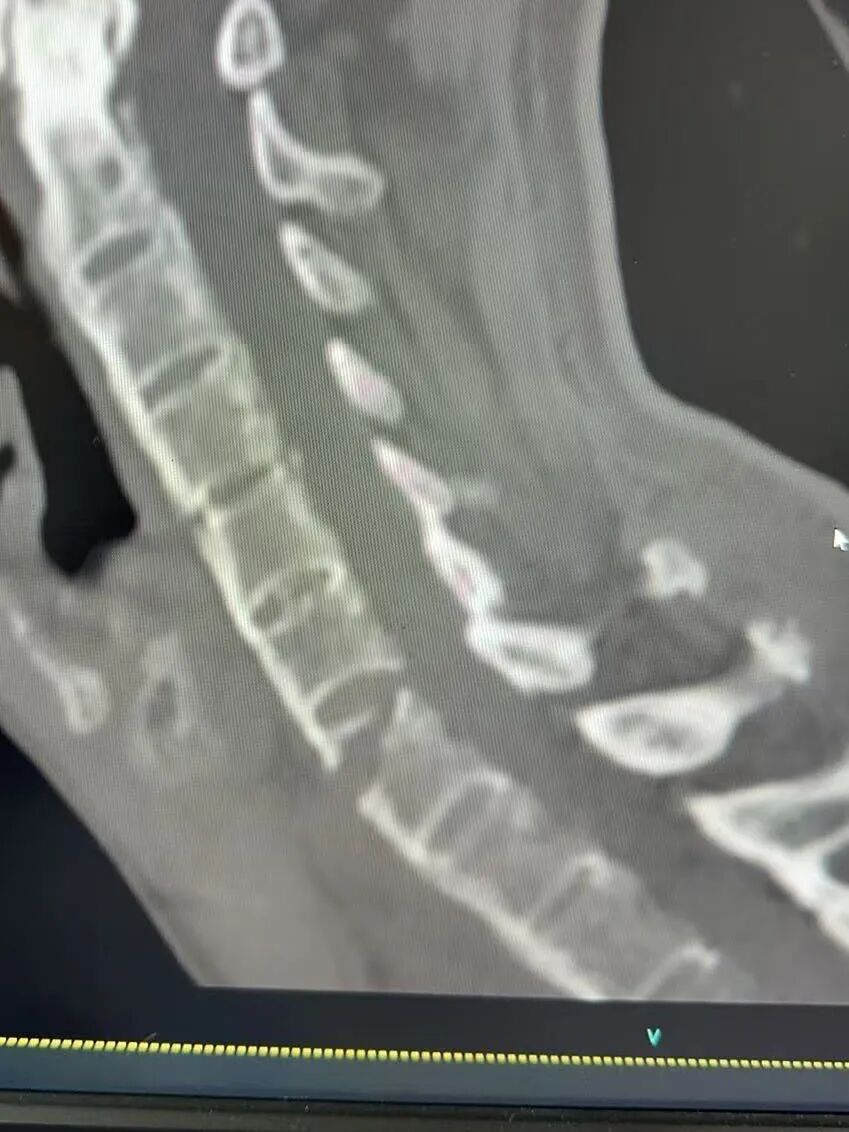

(手术前后X片检查对比)

整场手术历时约3小时,手术团队全神贯注,按照既定的手术方案,顺利完成了骨折复位、内固定植入等关键操作。手术过程中,每一个步骤都严谨有序,每一个细节都处理得恰到好处。经过3个小时的努力,手术终于成功完成,未发生任何并发症。

手术前后的X片对比显示,骨折端复位良好,内固定位置精准。这一结果让所有参与手术的医护人员都松了一口气,也为王先生的后续康复打下了坚实基础。手术的成功,不仅是手术团队精湛医术的体现,更是多学科协作的胜利。